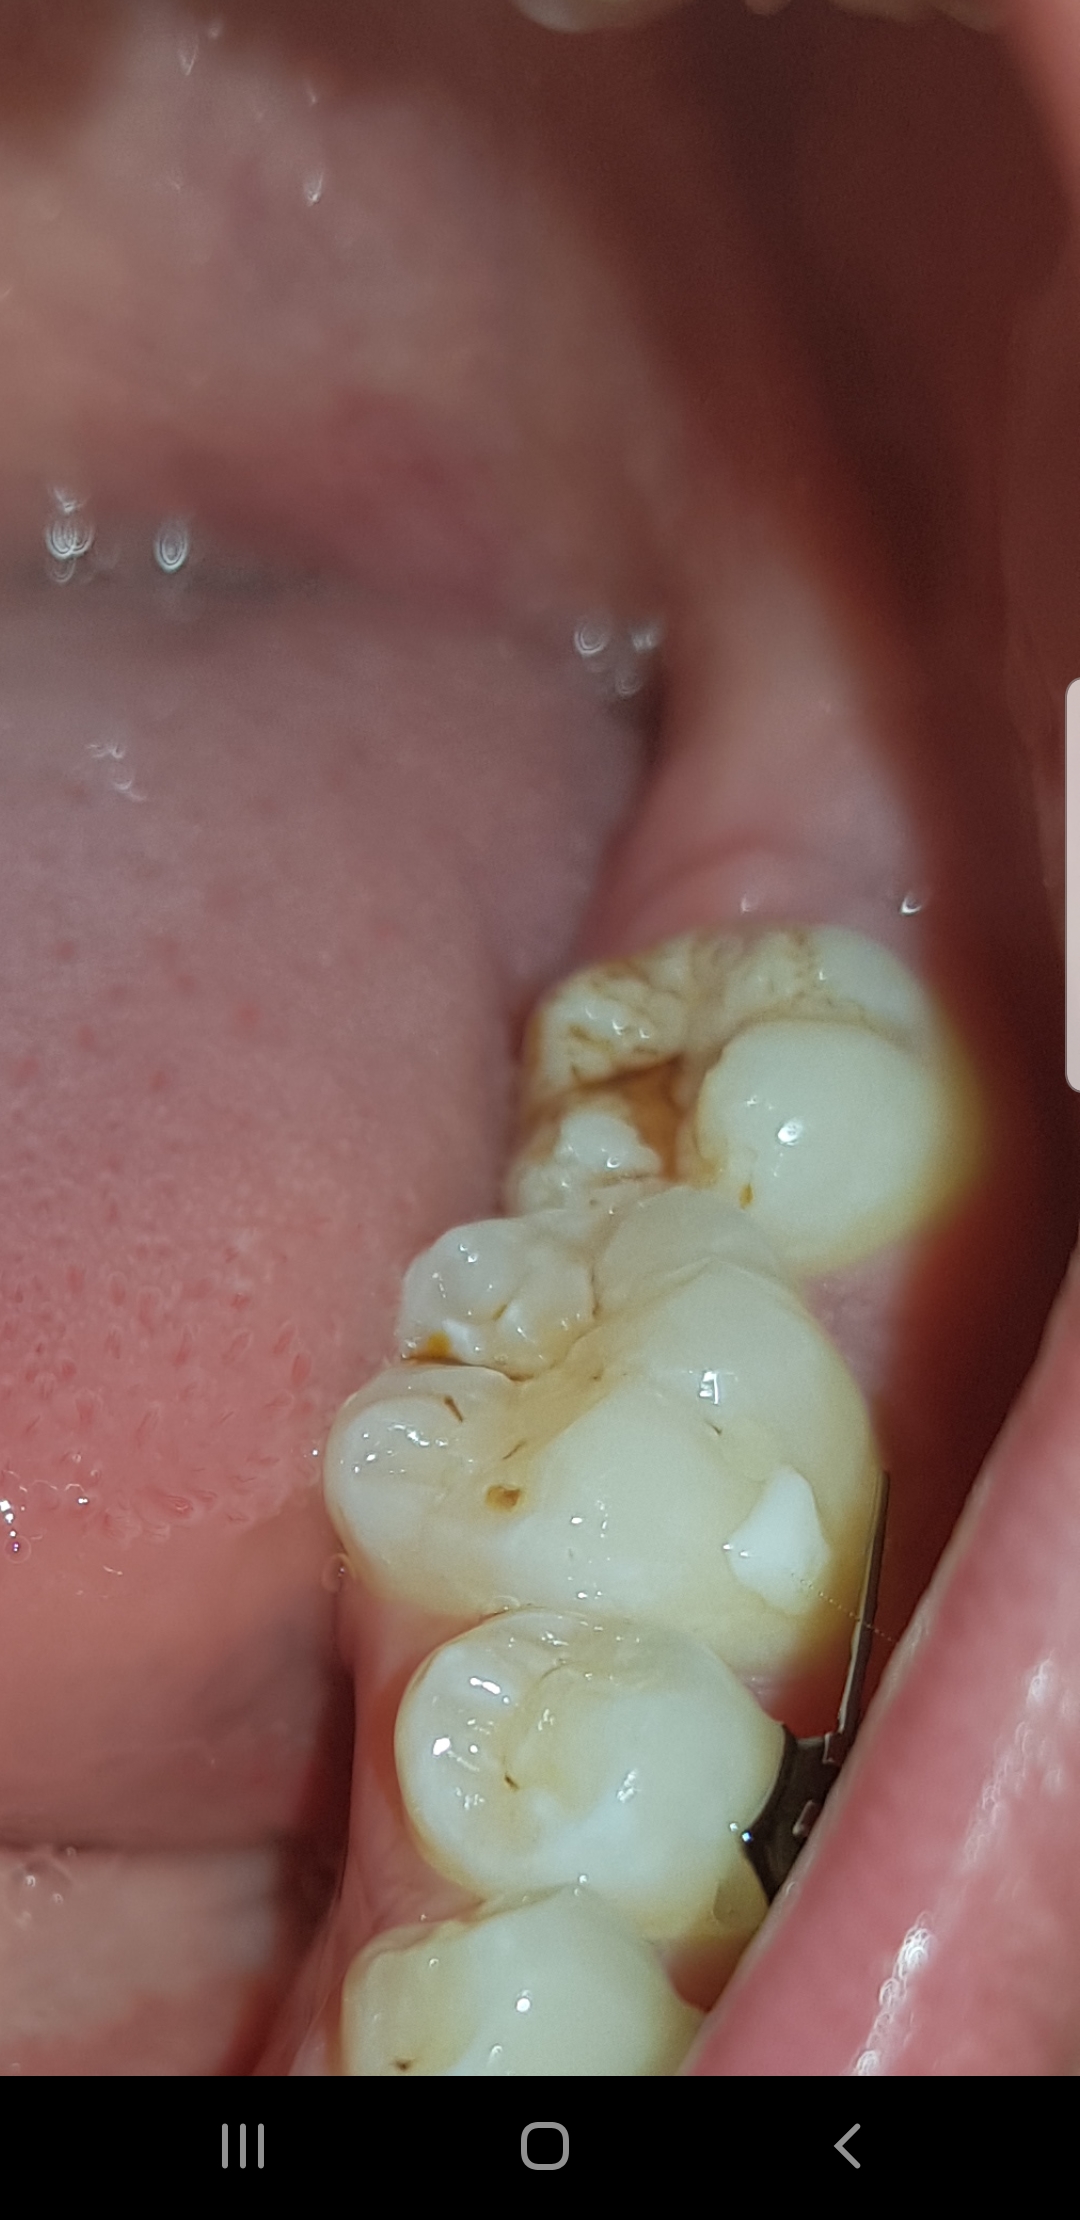

(© gangliu10 iStock) Oft sind es gerade die Backenzähne, die von uns am wenigsten Aufmerksamkeit beim Putzen und bei der Mundhygiene bekommen Das liegt vor allem an ihrer schwer zugänglichen Lage und der beschränkten Sicht, die wir vor einem Spiegel haben. Ein Loch im Zahn mit Gold zu füllen ist jedoch deutlich aufwendiger als beispielsweise mit Kunststoff Ein präziser Abdruck des Loches ist nötig um die Füllung passgenau anzufertigen Diese wird dann anschließend mit Spezialkleber oder gar Zement im Zahn befestigt. Zahn, Mund, Kieferkrankheiten / Zahnärztliche Notfälle / / Komplikationen nach Zahnextraktion / IN DIESEM THEMA meist Weisheitszähnen, auf Typischerweise beginnen die Schmerzen am 2 oder 3 postoperativen , strahlen zum Ohr aus und dauern von wenigen en bis zu vielen Wochen an.

Der Zahn selbst schmerzt nämlich nicht, er besteht aus schützendem, sehr hartem Zahnschmelz und etwas weicherem Zahnbein (Dentin) Nur die Nerven und Blutgefäße (Pulpa), die über die Zahnwurzel den Zahn versorgen und lebendig erhalten, sind schmerzempfindlich Dentin besteht, ähnlich wie Haare oder das Geweih eines Tieres, aus Hornsubstanz. (© gangliu10 iStock) Oft sind es gerade die Backenzähne, die von uns am wenigsten Aufmerksamkeit beim Putzen und bei der Mundhygiene bekommen Das liegt vor allem an ihrer schwer zugänglichen Lage und der beschränkten Sicht, die wir vor einem Spiegel haben. Re seitl Zahnabriss am Backenzahn hier passt meine Frage gerade dazu vor knapp 2 Jahren hatte ich hier schon mal angefragt Mein Zahnarzt wollte den Backenzahn ziehen und ich hatte keinen Grund darin gesehen Er hatte noch eine Füllung reingemacht, wodurch die aktuellen Schmerzen weg waren Jetzt ist durch die dünne Wandung der größte Teil des Zahns schmerzlos abgebrochen.